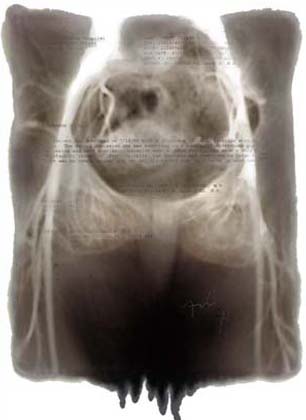

2003: As the body becomes fragile, what becomes of the self?

These images were shown in my MFA Thesis show at the Mass College of Art. In the first six images, I used the computer to combine my medical records with x-rays. The edges were created by encouraging the ink to run. The other four images are my x-rays that were modified in the computer and then printed large (2' x 4'). All images are inkjet prints on Vellum.